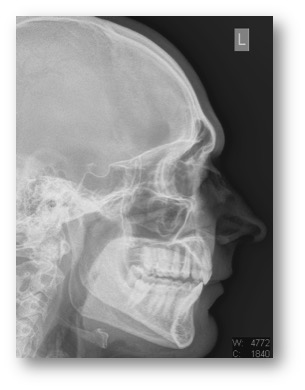

- Shaving Down Brow Ridge with Rhinoplasty

- Softening Features- Left

- Right View

- Shaving Brow Ridge